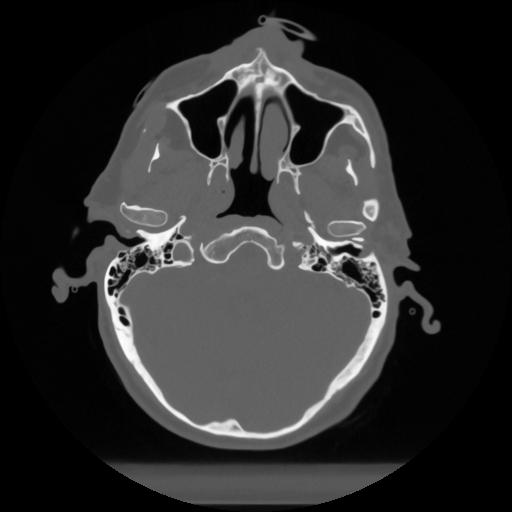

12 P.BLANDAS,,Vol,0.5,P.BLANDAS,,